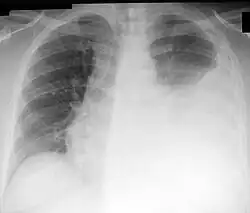

Chest X-ray showing a left-sided pleural effusion (right side of image). This can be treated with thoracentesis. | |

Thoracentesis /ˌθɔːrəsɪnˈtiːsɪs/, also known as thoracocentesis (from Greek θώραξ (thōrax, GEN thōrakos) 'chest, thorax' and κέντησις (kentēsis) 'pricking, puncture'), pleural tap, needle thoracostomy, or needle decompression (often used term), is an invasive medical procedure to remove fluid or air from the pleural space for diagnostic or therapeutic purposes. A cannula, or hollow needle, is carefully introduced into the thorax, generally after administration of local anesthesia. The procedure was first performed by Morrill Wyman in 1850 and then described by Henry Ingersoll Bowditch in 1852.[1]

This procedure is indicated when unexplained fluid accumulates in the chest cavity outside the lung. In more than 90% of cases, analysis of pleural fluid yields clinically useful information. If a large amount of fluid is present, then this procedure can also be used therapeutically to remove that fluid and improve patient comfort and lung function.

The most common causes of pleural effusions are cancer, congestive heart failure, pneumonia, and recent surgery. In countries where tuberculosis is common, this is also a common cause of pleural effusions.

While chest X-ray has traditionally been performed to assess for pneumothorax following the procedure, it may no longer be necessary to do so in asymptomatic, non-ventilated persons given the widespread use of ultrasound to guide this procedure.[11]